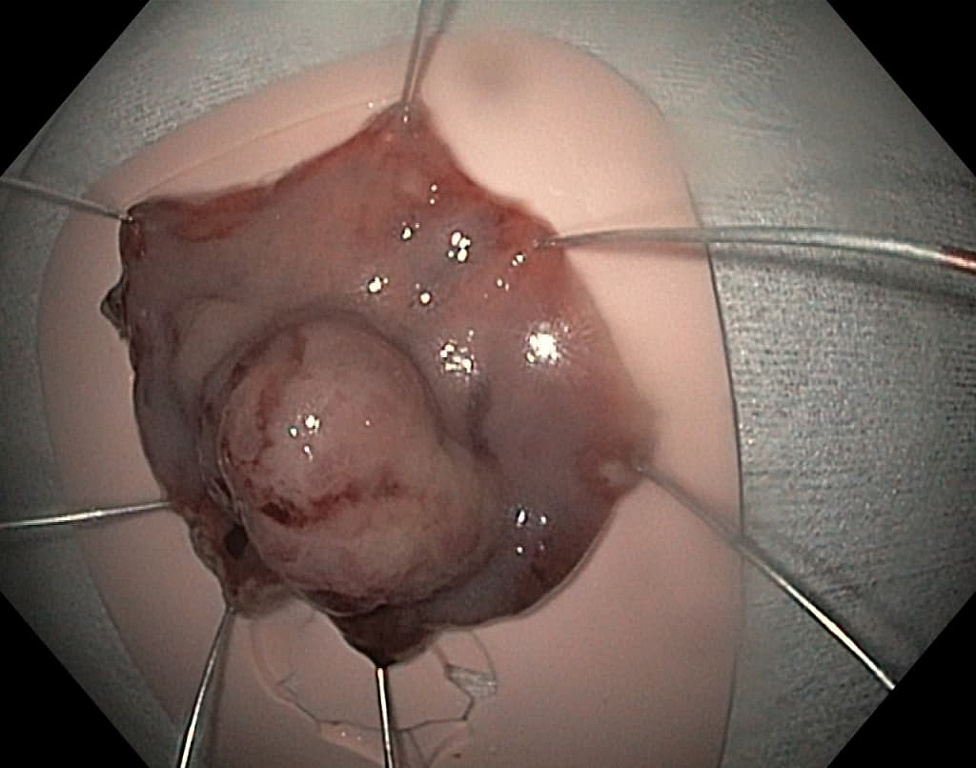

удаленный препарат методом диссекции в подслизистом слое.jpgПо современным представлениям, необходимо выполнить эрадикацию H.pylori с последующей оценкой между 3 и 6 месяцами после терапии для подтверждения успешного лечения. Во многих случаях оставленные маленькие гиперпластические полипы могут регрессировать или исчезнуть вовсе. Пациенты с III и IV стадиями по классификации OLGA (умеренная диффузная или тяжелая атрофия слизистой, наряду с распространенной кишечной метаплазией) должны проходить последующее эндоскопическое наблюдение не реже 1 раза в год, так как риски развития рака желудка в данном случае повышаются более чем в 6 раз.

Крупные экзофитные (выступающие) полипы на широком основании или плоские образования, которые невозможно удалить эндопетлей, подвергаются технически более сложному варианту эндоскопического удаления – диссекции в подслизистом слое. Данный вид операции направлен на радикальное удаление образования единым блоком: после создания «гидростатической подушки» выполняется циркулярный разрез вокруг образования специальными инструментами, после чего рассекаются соединительнотканные сплетения подслизистого слоя с полной ликвидацией патологического очага.